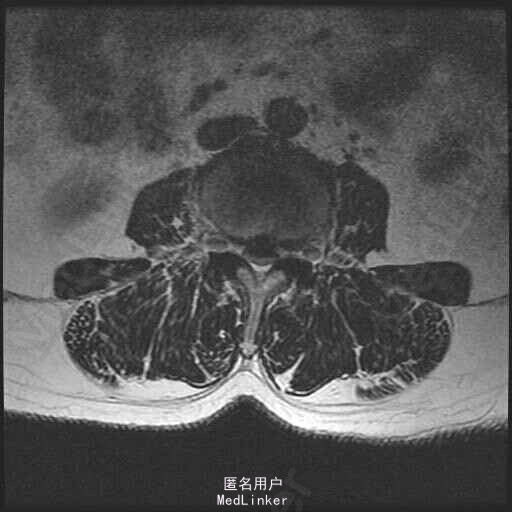

查体:脊柱无明显侧弯畸形,腰部无压痛,双上肢肌力肌张力可,无异常感觉,左下肢臀部及双下肢足背部麻木感。双侧键反射减弱,股四头肌,髂腰肌肌力四级,病理征阴性。直腿抬高试验左侧60度,右侧65度。 辅助检查:MR显示:腰椎退行性改变,L3-4.L4-5,L5-S1椎间盘突出,椎管狭窄。

诊断:L3-4.L4-5椎间盘突出,椎管狭窄 治疗: 腰椎后路减压融合内固定术